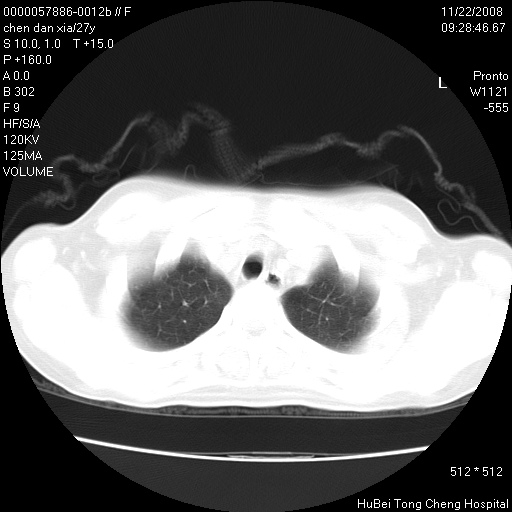

考虑双肺粟粒性肺tb,右侧胸膜增厚.

右下肺见片絮状影,两肺野内分布不均的小结节影,结核并肺内播散可能性大,建议结合实验室检查 .

右下肺纹理模糊;纵隔可见肿大淋巴节;右心缘旁结节,边缘光滑,纵隔窗病变范围较肺窗明显小,首先考虑右下肺结核,不排外淋巴瘤

右侧前胸壁胸膜局限性肥厚(胸膜炎?)其他的强化观察.

下肺结节,结节内钙化,肺门纵隔淋巴肿大 结核可能性大

以下是引用hyhxn在2008-11-22 18:02:00的发言:[br]考虑双肺粟粒性肺tb,右侧胸膜增厚.

似有粟米状结节。考虑粟粒型肺结核?